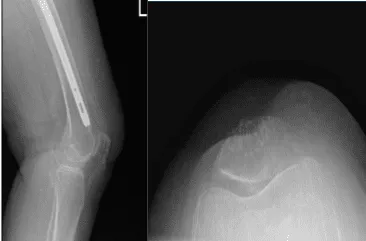

Se presentaron y revisaron radiografías, el fémur de la paciente curó la fractura intertrocantérica, pero se detectaron leves cambios degenerativos osteoartríticos en la rodilla. Hablamos sobre la posibilidad de la etiología del dolor de rodilla y las opciones de tratamiento.

Radiografía de la rodilla izquierda con rótula